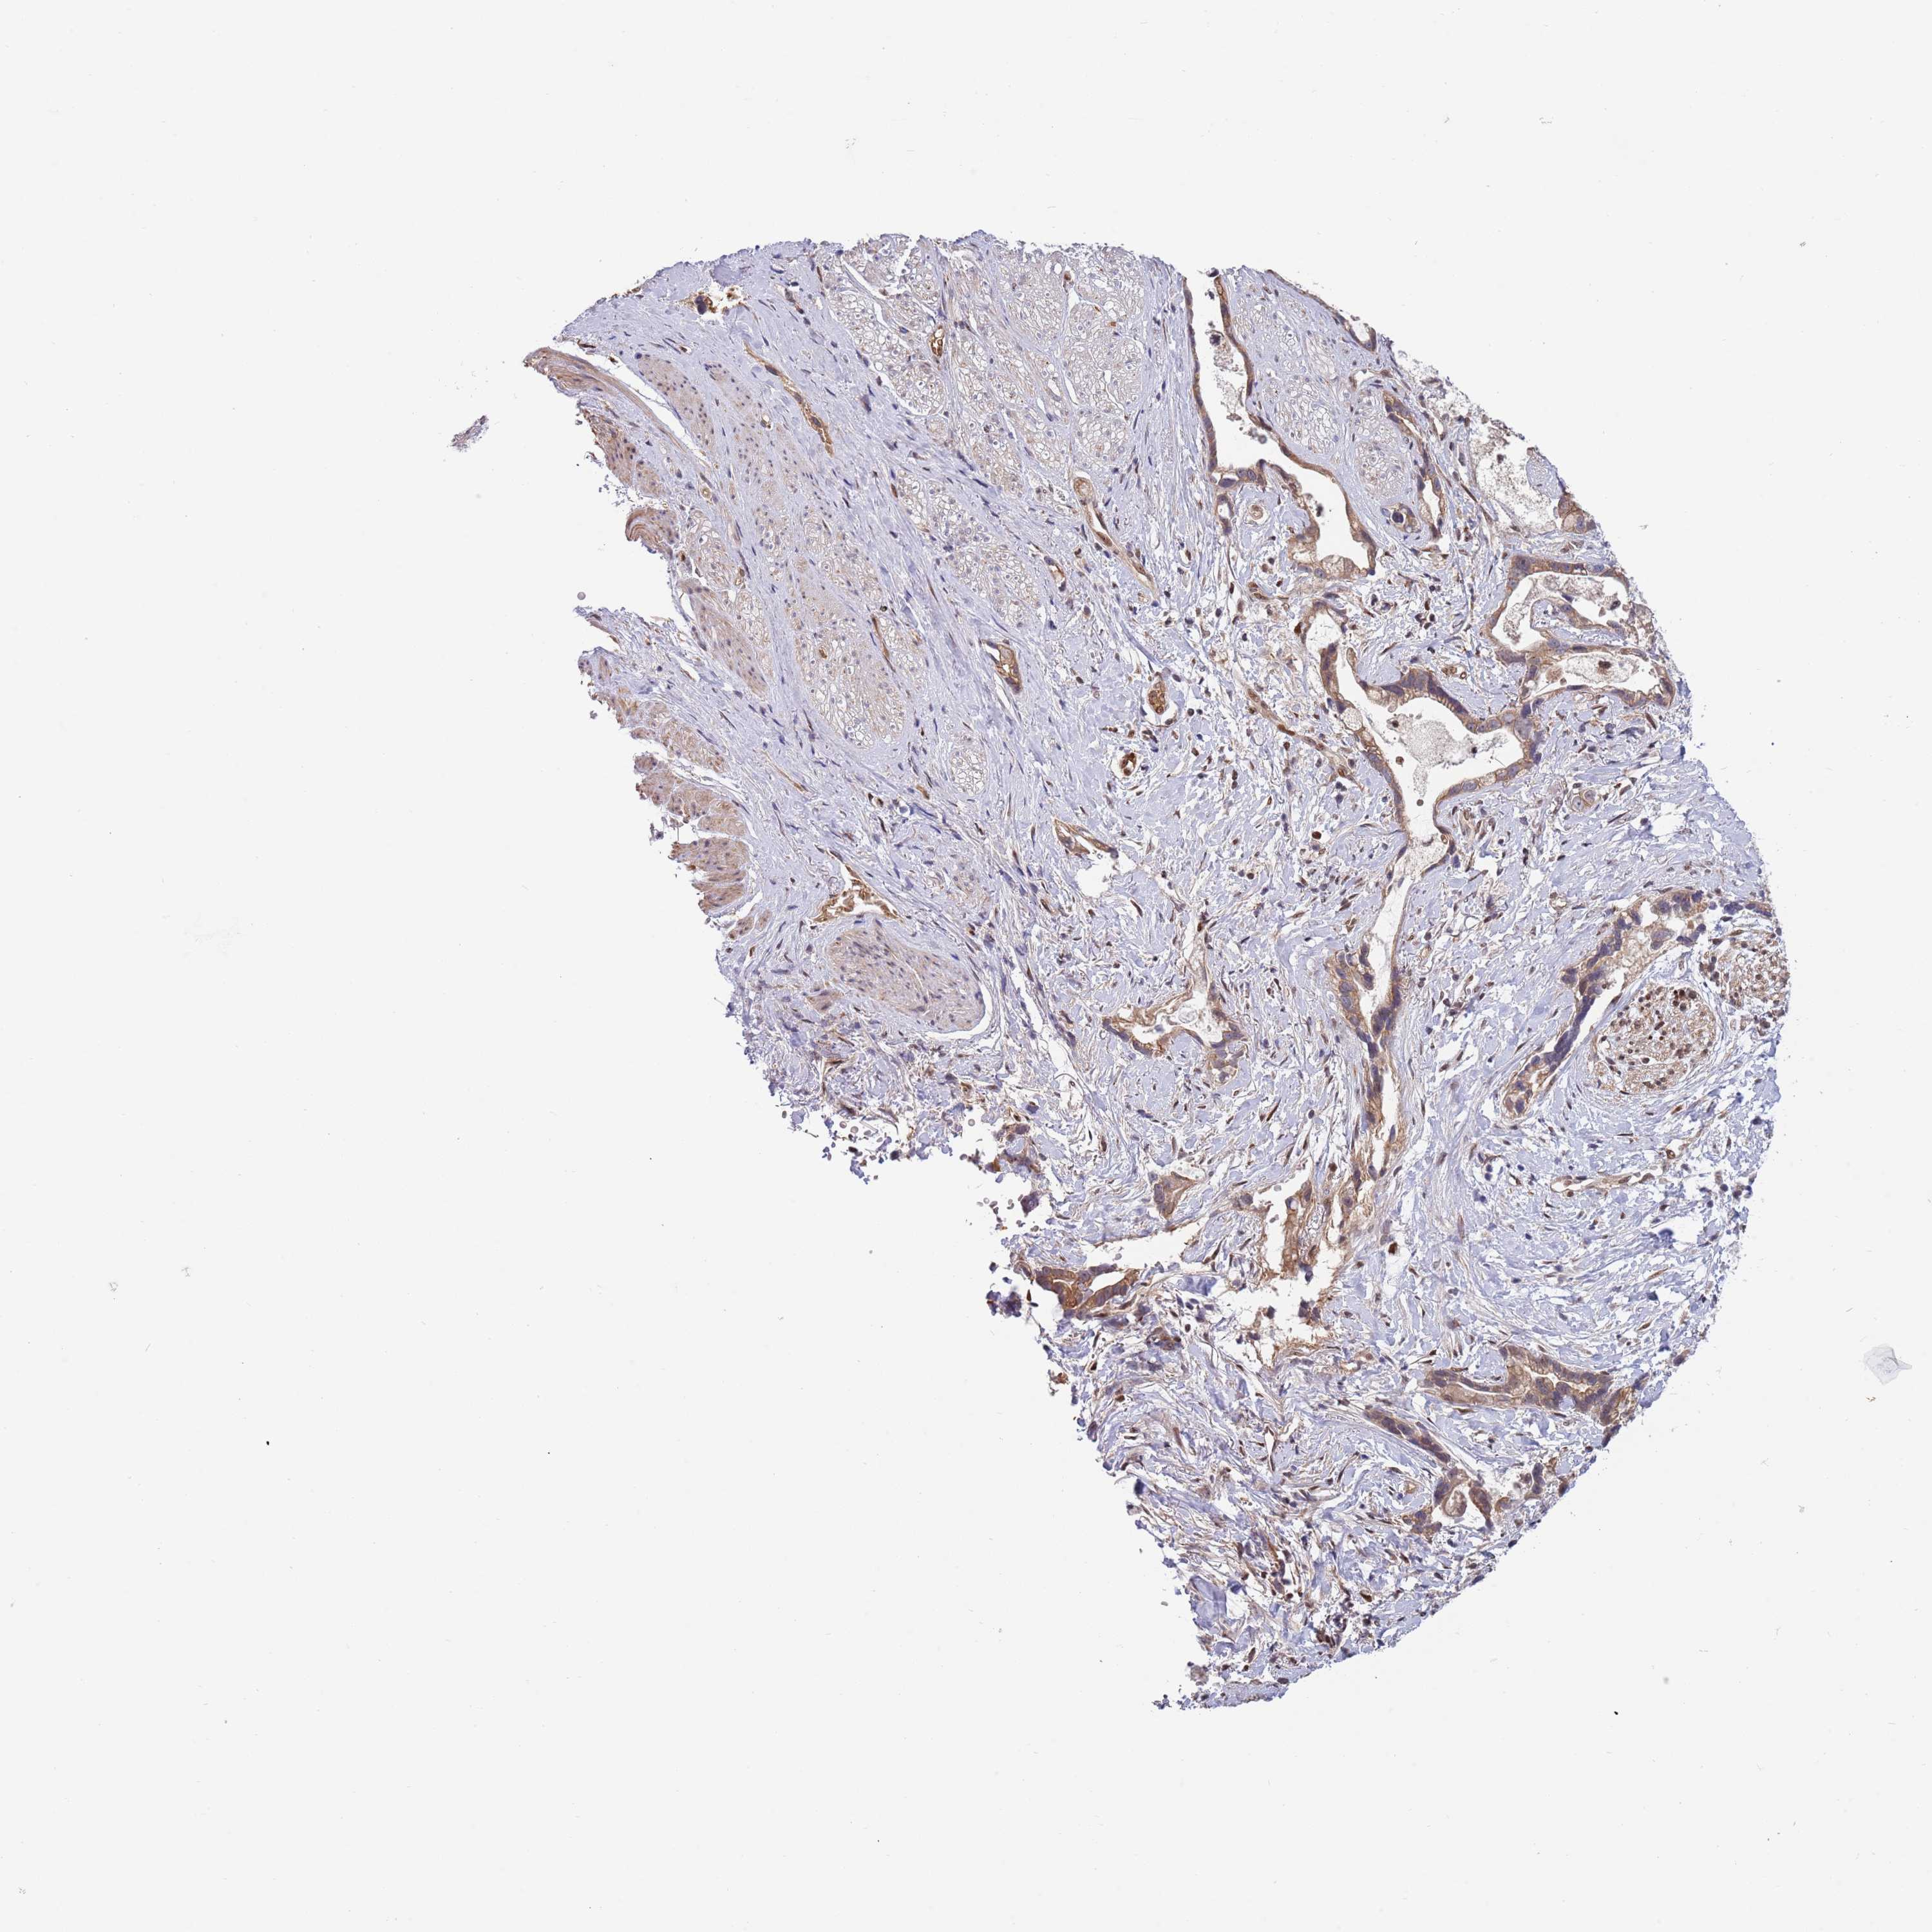

STOMACH CANCER - Protein expressioni

A mouse-over function shows sample information and annotation data. Click on an image to view it in a full screen mode. Samples can be filtered based on level of antibody staining by selecting one or several of the following categories: high, medium, low and not detected. The assay and annotation is described here.

Antibody stainingi

Antibody staining in the annotated cell types in the current human tissue is reported as not detected, low, medium, or high, based on conventional immunohistochemistry profiling in selected tissues. This score is based on the combination of the staining intensity and fraction of stained cells.

Each image is clickable and will lead to virtual microscopy that enables deeper exploration of all samples and also displays staining intensity scores, fraction scores and subcellular localization as well as patient and tissue information for each sample.

Antibody HPA047881

Staining

High

Medium

Low

Not detected

Intensity

Strong

Moderate

Weak

Negative

Quantity

>75%

75%-25%

<25%

None

Location

Nuclear

Cytoplasmic/membranous

Cytoplasmic/membranous,nuclear

Adenocarcinoma, NOS